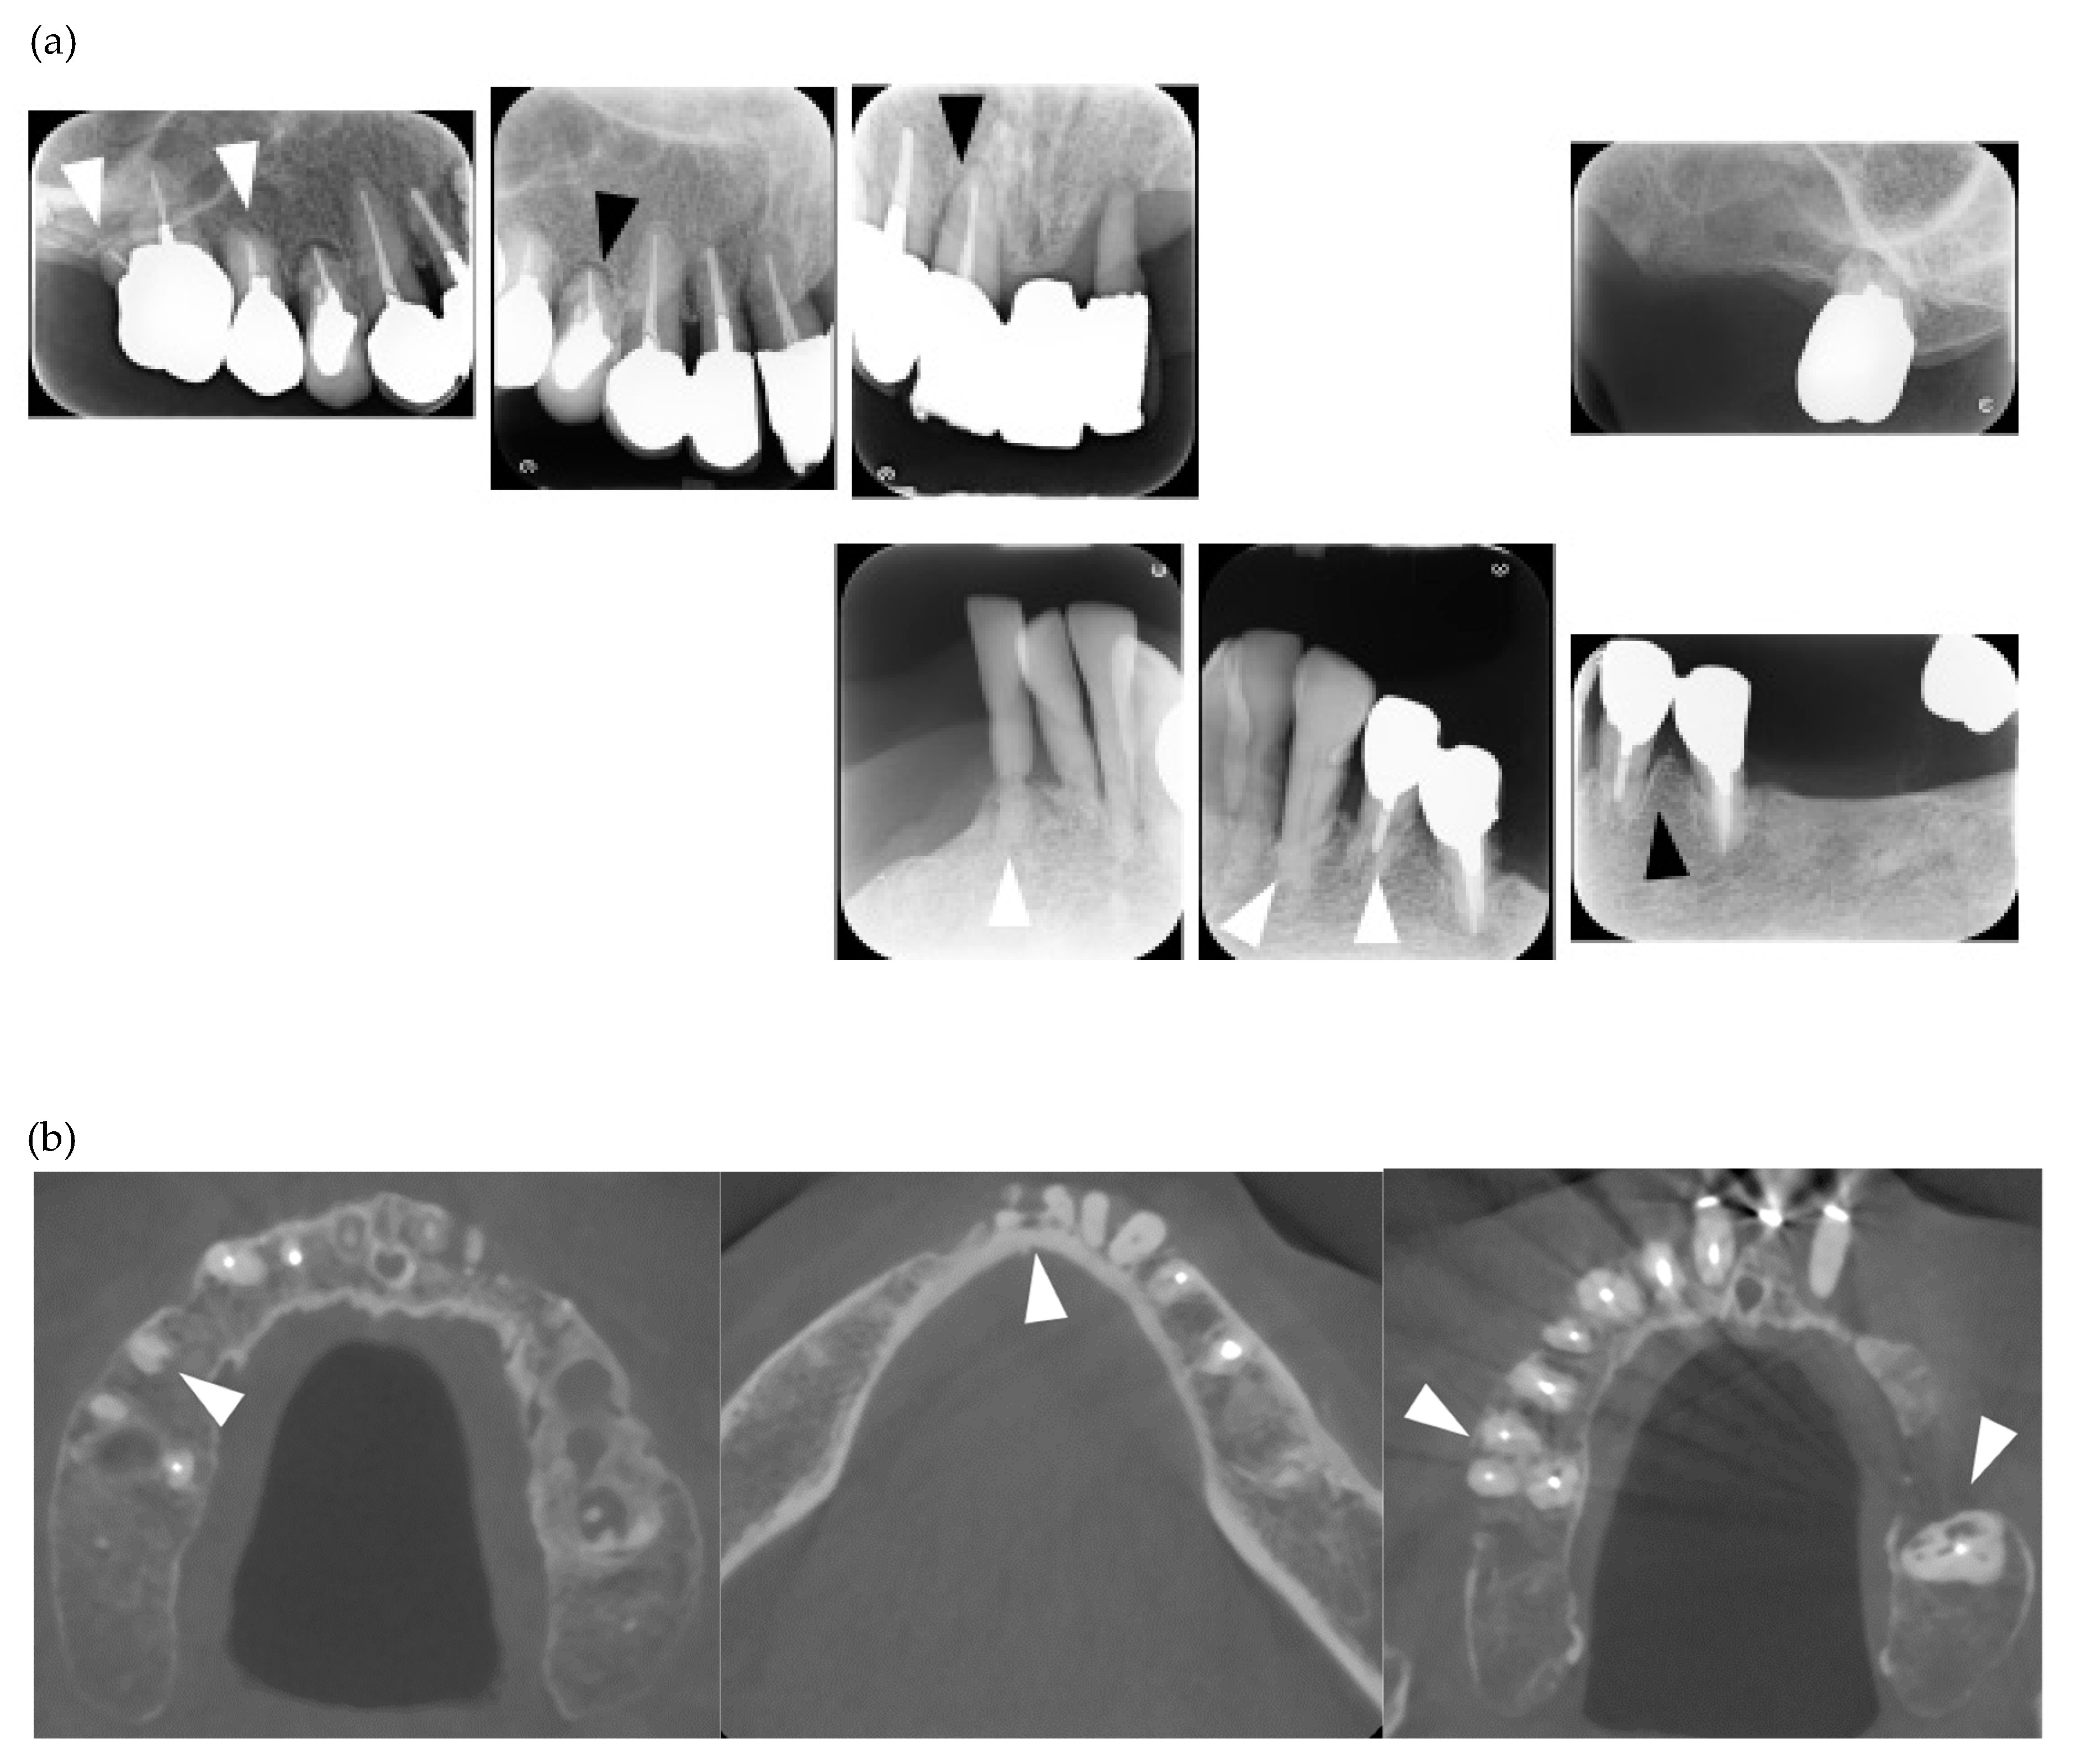

| 1 | F | 24 | lc | Y | Y | N | Y | Y | Y | Y | Y | Y | Y | / | / | / | Y | Y | N | Y | Y | Y | N | centro/RF | a case report [6]/occlusal force, 77.4N |

| 2 | F | 40 | dc | Y | Y | Y | Y | N | N | N | Y | N | Y | / | N | N | Y | Y | Y | Y | N | Y | Y | Scl-70/RF | |

| 3 | F | 23 | dc | Y | Y | Y | Y | N | Y | N | Y | Y | Y | / | / | / | Y | Y | Y | Y | Y | Y | Y | ANA/Scl-70/SS-A | Orthodontic treatment |

| 4 | F | 11 | dc | Y | Y | Y | Y | Y | N | N | N | N | Y | / | / | / | Y | Y | Y | N | N | Y | Y | ANA/Scl-70 | calcification in PDL space/Orthodontic treatment |